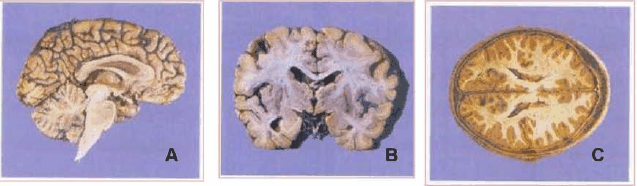

Assinale a alternativa que identifica

CORRETAMENTE

os planos de corte utilizado para a visualização das estruturas anatômicas abaixo.

A - sagital; B - frontal; C - transversal.

A - transversal; B- frontal; C - sagital.

A - sagital; B - transversal; C - frontal.

A - transversal; B - sagital; C - frontal.

A - frontal; B - sagital; C - transversal.